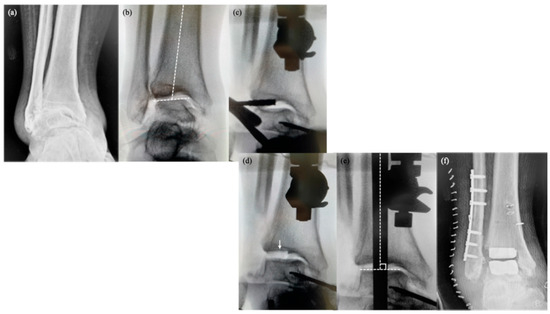

Background: Covering the defects around the calcaneus is still a largely debatable subject. In the classical view, the defects at the level of the foot can be treated only by a free flap. In a modern approach, it has been observed that for small or m...